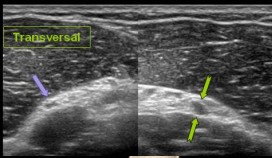

위에 있는 초음파 이미지에서

좌측 보라색 화살표는

정상 신경의 단면이고

우측 노란색 화살표는

압박되어 퉁퉁 부어있는

마비된 신경의 단면입니다.